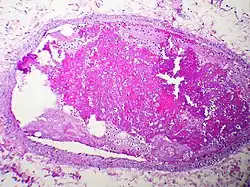

thromboembolism, the thrombus (blood clot) from a blood vessel is completely or partially detached from the site of thrombosis (clot). The blood flow will then carry the embolus (via blood vessels) to various parts of the body where it can block the lumen (vessel cavity) and cause vessel obstruction or occlusion. The free-moving thrombus is called an embolus.[7] A thrombus is always attached to the vessel wall and is never freely moving in the blood circulation. This is also the key difference for pathologists to determine the cause of a blood clot, either by thrombosis or by post-mortem blood clot. Vessel obstruction will then lead to different pathological issues such as blood stasis and ischemia. However, not only thromboembolism will cause the obstruction of blood flow in vessels, but also any kind of embolism is capable of causing the same problem.